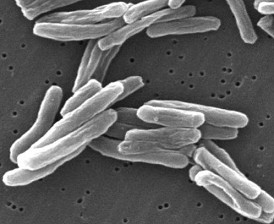

Robert Koch is infecting laboratory animals with TB tuberculous tissue resp. with TB threads. These animal tests are performed with rabbits and guinea pigs (p.40). But the TB threads cannot be increased in the nutrient solutions (p.40-41), but later - as will be detected - can be increased in the blood serum of different animals. Koch can take photos of the TB threads by the microscope presenting the photos in 1882 (p.41).

With this procedure Koch has isolated the TB pathogen. He now claims the following equation:

Tuberculosis pathogen (threads) [15]

"Pathogen + host = illness" (p.51).

The investigations show that only 5 to 8% of the TB infected people also suffer an outbreak of TB (p.42). The immune system is killing the pathogen, but the researchers don't see this. The research how this functions precisely is simply not happening (p.43).

Another study by Koch proves that ultraviolet radiation is killing the TB pathogen. Therefore sun light principally is enough as a prevention against TB, but also this is not seen by the researchers.